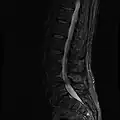

MRI

MRI lumbar spine with degeneration (sagittal T2 FRFSE)

MRI lumbar spine with degeneration (sagittal T1 FSE)

MRI lumbar spine with degeneration (sagittal FAST STIR)

MRI lumbar spine pre-hemilaminectomy (sagittal T2 FRFSE)

MRI lumbar spine pre-hemilaminectomy (sagittal T1 FSE)

MRI lumbar spine pre-hemilaminectomy (sagittal FAST STIR)

MRI lumbar spine post-hemilaminectomy (sagittal T2 FRFSE)

MRI lumbar spine post-hemilaminectomy (sagittal T1 FSE)

Contrast MRI lumbar spine post-hemilaminectomy (sagittal T1 FSE FS)